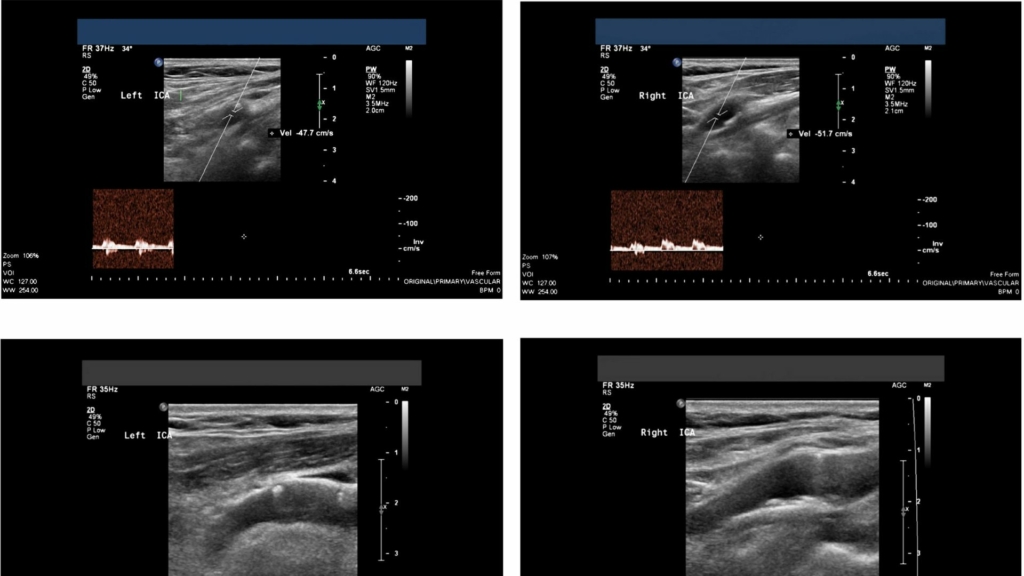

- ตรวจหลอดเลือดแดงที่คอทั้ง 2 ข้าง